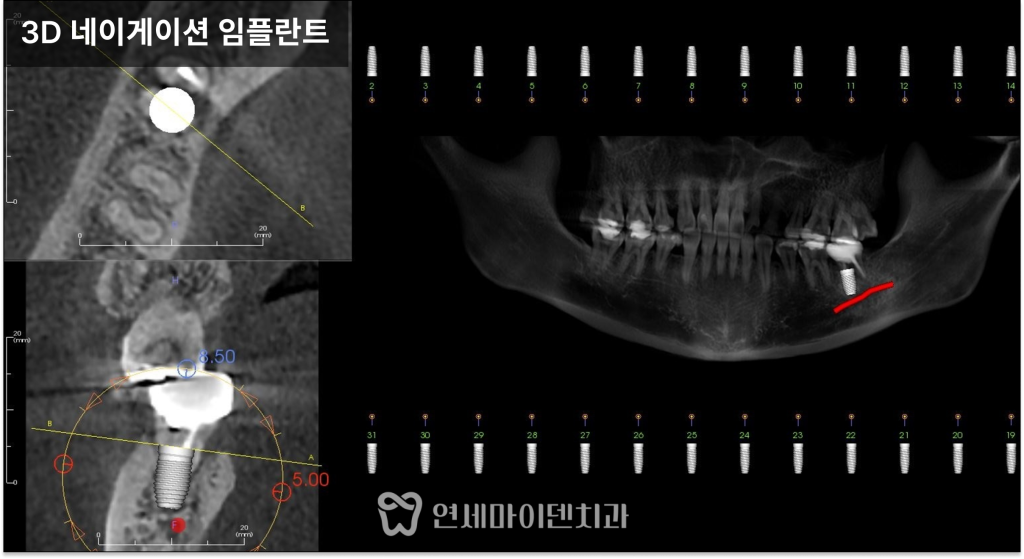

발치 즉시 임플란트를 선택한 이유

임신 준비 중이라는 상황을 고려해

치료 기간을 단축하는 것이 중요했습니다.

그래서 발치와 동시에

임플란트를 식립하는

‘발치 즉시 임플란트’를 계획했습니다.

이 방법은 염증을 완전히 제거한 뒤

남아 있는 건강한 뼈를 이용해

즉시 고정력을 확보할 수 있을 때 가능한 치료입니다.

특히 아래 어금니 부위는

하치조 신경관이 지나가기 때문에

위치와 깊이를 매우 신중하게 설정해야 합니다.

염증 조직을 깨끗하게 제거하고

신경 위치를 고려해 식립을 진행했으며,

한 번의 수술로 발치와 임플란트를

모두 마무리했습니다.